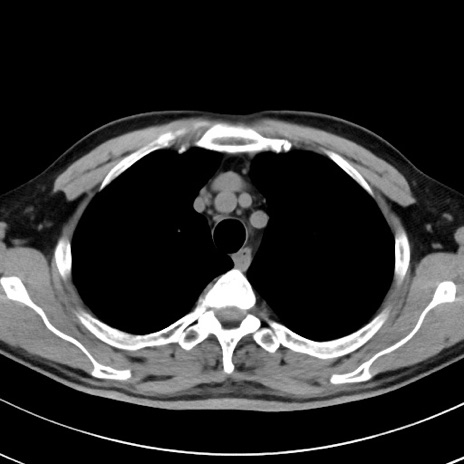

【腹部TIPS】症例29 参考症例 CT(横断像)

症例

70歳代男性